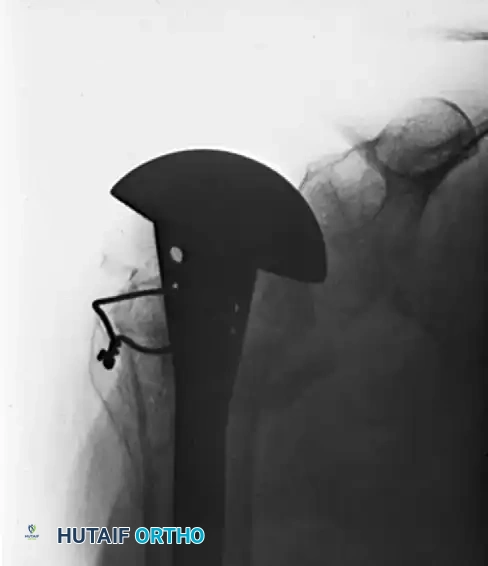

Figure A: Preoperative appearance on admission demonstrating a complex four-part fracture-dislocation with an ununited fracture at the anatomical neck of the humerus.

The Neer I prosthesis (hemiarthroplasty) relies heavily on the anatomical healing of the greater and lesser tuberosities around the implant to restore rotator cuff function. Meticulous tuberosity mobilization, heavy suture fixation through the prosthesis fin, and securement to the humeral shaft are critical steps.

Figure B: Solid union and stable fixation 6 months postoperatively following reconstruction with a Neer I prosthesis, yielding satisfactory clinical function.